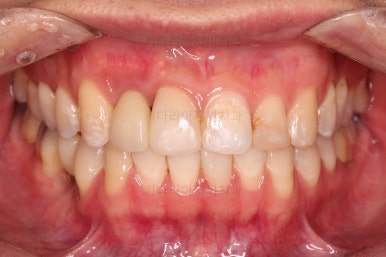

임플란트 완료시 모습인데요.

임플란트 식립부터 완료까지 시간이 걸리다보니 최종 종료까지는 총 19개월이 걸렸습니다.

교합도 잘 맞고 임플란트도 잘 완성되었네요.

매복치아도 손상 없이 잘 배열이 되었고, 교합도 좋게 마무리 되었습니다.

전후 비교입ㄴ디ㅏ.

크게 바꿀 필요가 없었던 얼굴모습은 거의 그대로 유지를 했고요. 웃을 때의 치열의 정렬된 느낌은 개선되었습니다.

매복치, 유치, 결손치 등 기능적인 부분들이 모두 잘 개선되었습니다.